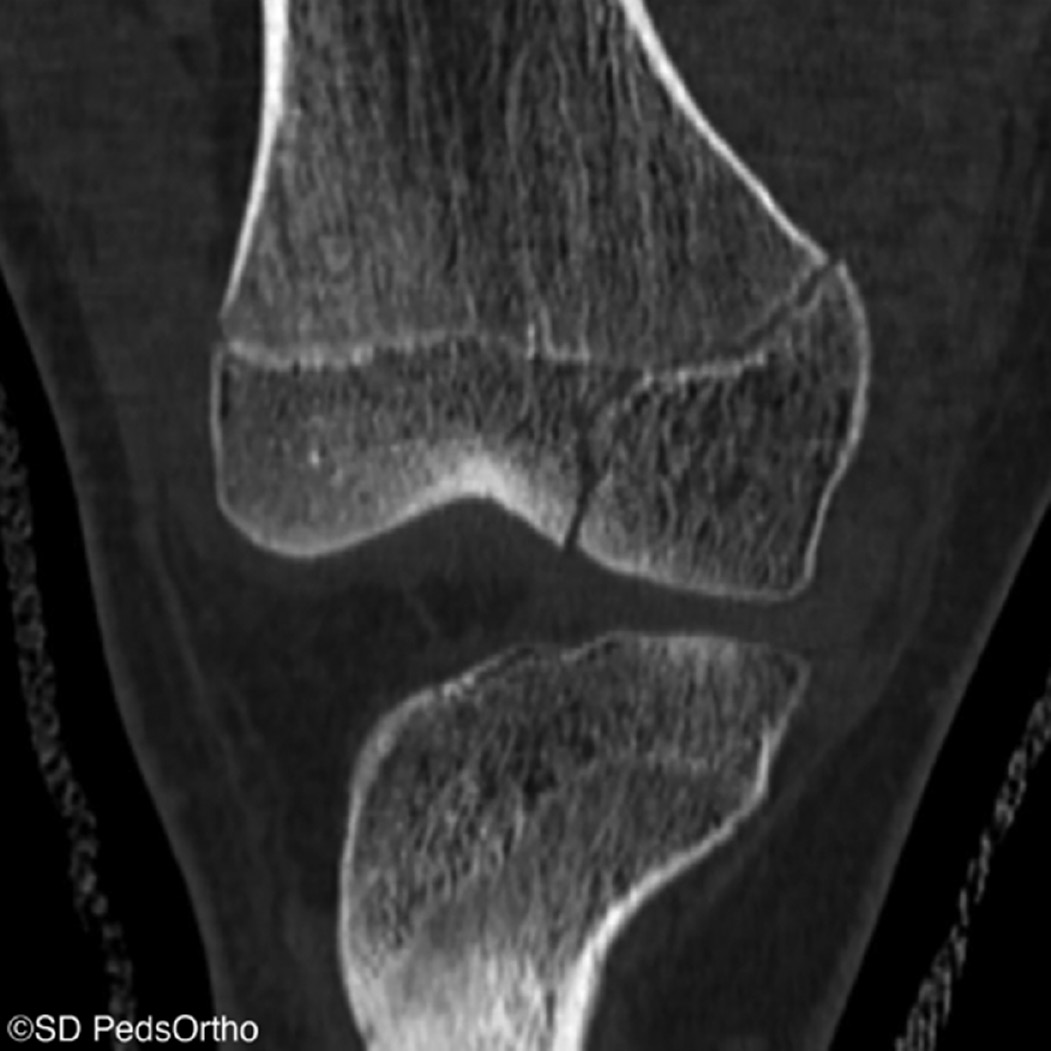

CT Imaging

CT scans aren’t routinely necessary for MCL tears but may be considered to evaluate the osseous architecture, a bony avulsion of the MCL, or in cases where a physeal injury is suspected (Figure 8).

Figure 8. Coronal CT image of a Salter-Harris III fracture of the medial femoral condyle in an adolescent patient presenting with a mechanism and examination concerning a proximal MCL injury.